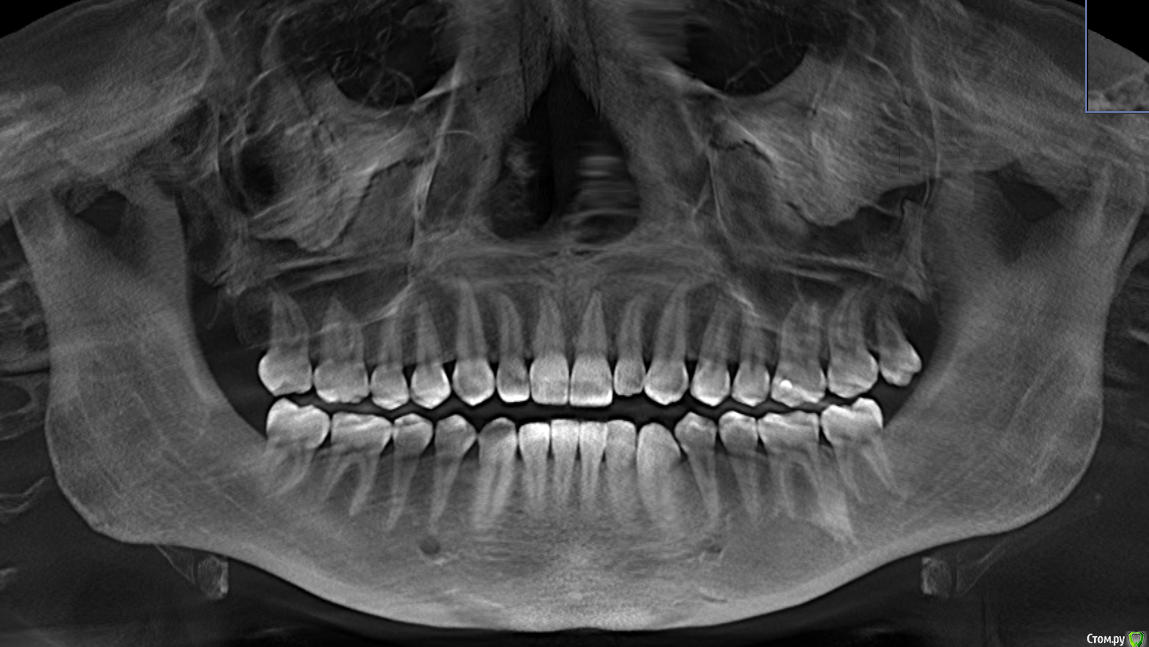

juliavesna Опубликовано 23 сентября, 2017 Автор Поделиться Опубликовано 23 сентября, 2017 Дорогие доктора!Снова пишу вам крик о помощи! Прикрепляю все, что есть и смогла сделать! Если нужно что-то еще - сделаю! Снимок после удаления нижних зубов мудрости. Консультации у врачей привели к следующим итогам. 1 вариант лечения - ношение мягкой капы около 3 месяцев, затем ношение жесткой капы до полугода, затем ортодонтическое лечение.2 вариант - сразу ортодонтическое лечение. (Только 1 врач из всех посещенных предложил такое лечение). Врач считает, что все мои проблемы с суставами вызваны неправильным суженным прикусом и положением зубов. Остальные ортодонты не брались за меня. По первому варианту я решила не тянуть и уже мне сделали мягкую капу, но проблема в том, что я не могу ее долго носить, на ночь не рискнула пока, так как она давит на мои кривые передние зубы и они начинают болеть. Еще раз пишу, что состояние суставов стало таким в течение последних полутора лет. Раньше таких конкретных проблем не было. Буду благодарна любым советам и комментариям. Ссылка на комментарий